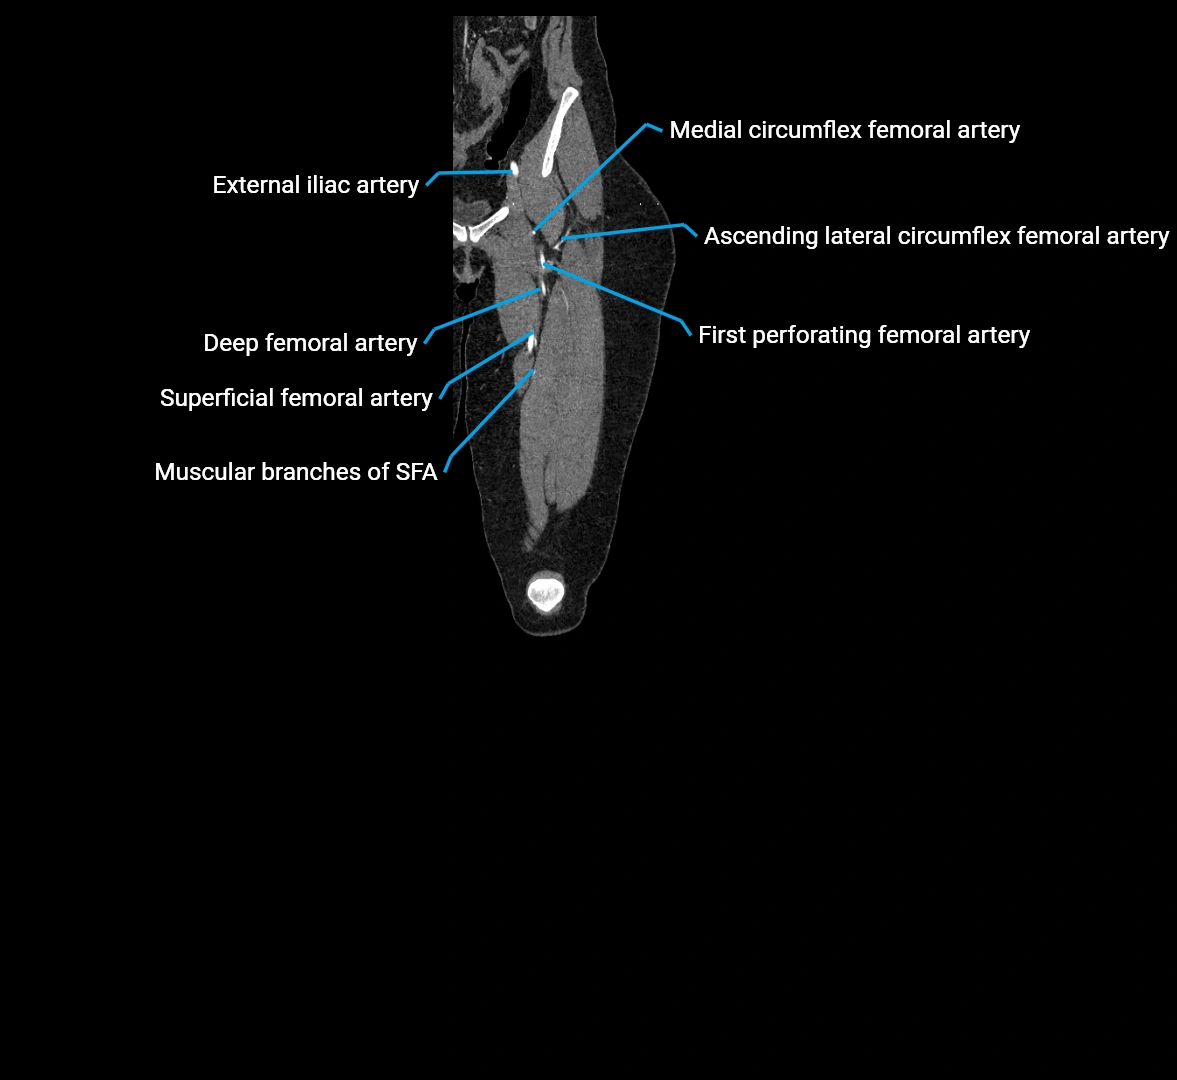

Contrast-enhanced CT (CTA):

• Gold standard for abdominal aortic imaging

• Provides excellent detail of lumen, wall, aneurysm, thrombus, and branch vessels

• Multiplanar and 3D reconstructions help in aneurysm measurement, stent graft planning, and dissection evaluation

• Detects acute rupture, traumatic injury, or occlusion with high sensitivity